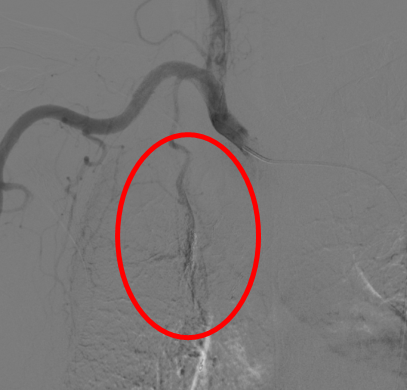

(肿瘤侵犯堵塞右肺动脉、上腔静脉)

右侧支气管动脉(肿瘤供血)栓塞后消失

右侧胸廓内动脉(肿瘤供血)栓塞后消失